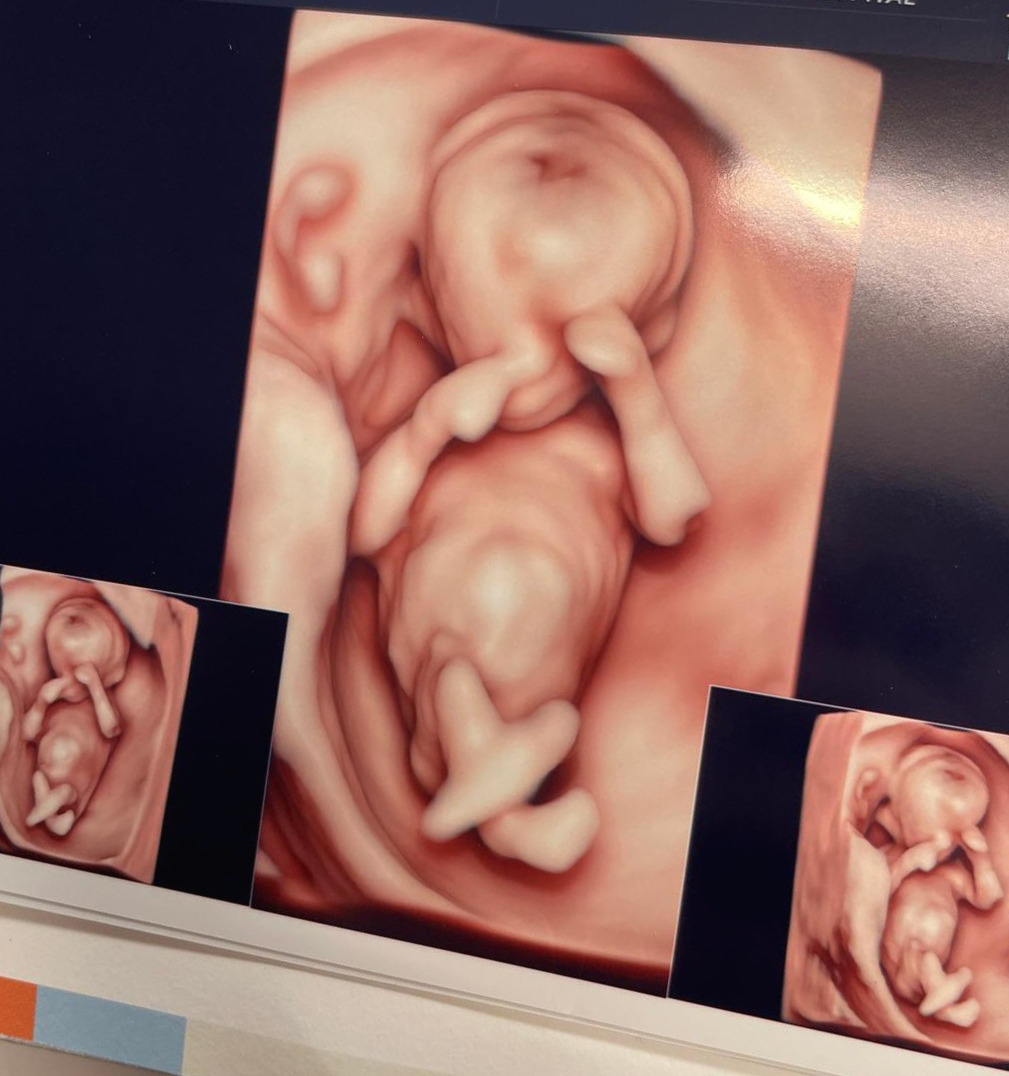

성별을 알 수 있는 초음파 검사날.

뱃속 아기는 웅크리고 낮잠을 잤다. 두 손으로 눈을 가리고 두 다리를 꼬고 자는 듯한 모양이 꽤 귀여웠다.

요리조리 각도를 재던 선생님은 초음파 기계로 배를 흔들어 아기를 깨우려 했고, 심지어는 내게 잠시 옆으로 누워 벨리댄스를 추듯 골반을 흔들어보라고 했다.

잠을 푹 자는 녀석을 보며 태어나면 '잠을 잘 재울 수 있겠구나' 싶은 희망적인(?) 수면교육의 기대감을 걸며, 나는 옆으로 누워 벨리댄스를 추듯 골반을 흔들었다.

그 틈에 깬 녀석의 다리 사이를 드디어 염탐할 수 있었다. 결과는 역시나... 아들이었다.

다리 꼬고 누운 녀석의 다리 사이... 뚜렷한 아들의 증거.!!!